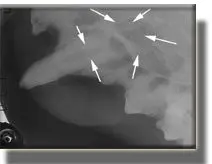

Radiograph of this tooth showing enlarged root canal and total destruction of most of the root, secondary to infection. This tooth could not be saved and was extracted. The patient felt much better within a few days.